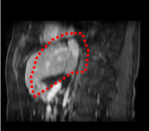

An example of CT/CBCT and MR/CBCT registration results are shown in figures 3 and 4, respectively. For both cases, the CBCT image (first column) was acquired intra-operatively after needle insertions and was employed as a reference for image registration. The pre-operative image is displayed before registration (second column), after PM-EA (third column) and after PM-EA+Evo (fourth column). The occurrence of patch shifts is reported for each spatial direction in panels (m–o): for each histogram, the shift with maximal occurrence is shown by the red dashed line. For panels (a–l), a ROI — manually defined on the CBCT image/encompassing the liver — is shown using red dash lines. Our visualization shows an improved correspondence of the contour of the liver with the manually defined liver boundary when the PM-EA solution is employed (see 3(c,g,k) and 4(c,g,k)). Moreover, an even better correspondence of the contour is observable using the PM-EA+Evo solution (see 3(d,h,l) and 4(d,h,l)).

Trans.

[X-Y]

CBCT

(a)

CT / No registration

(b)

CT / PM-EA

(c)

CT / PM-EA+Evo

(d)

Sag.

[X-Z]

(e)

(f)

(g)

(h)

Cor.

[Y-Z]

(i)

(j)

(k)

(l)

(m)

(n)

(o)